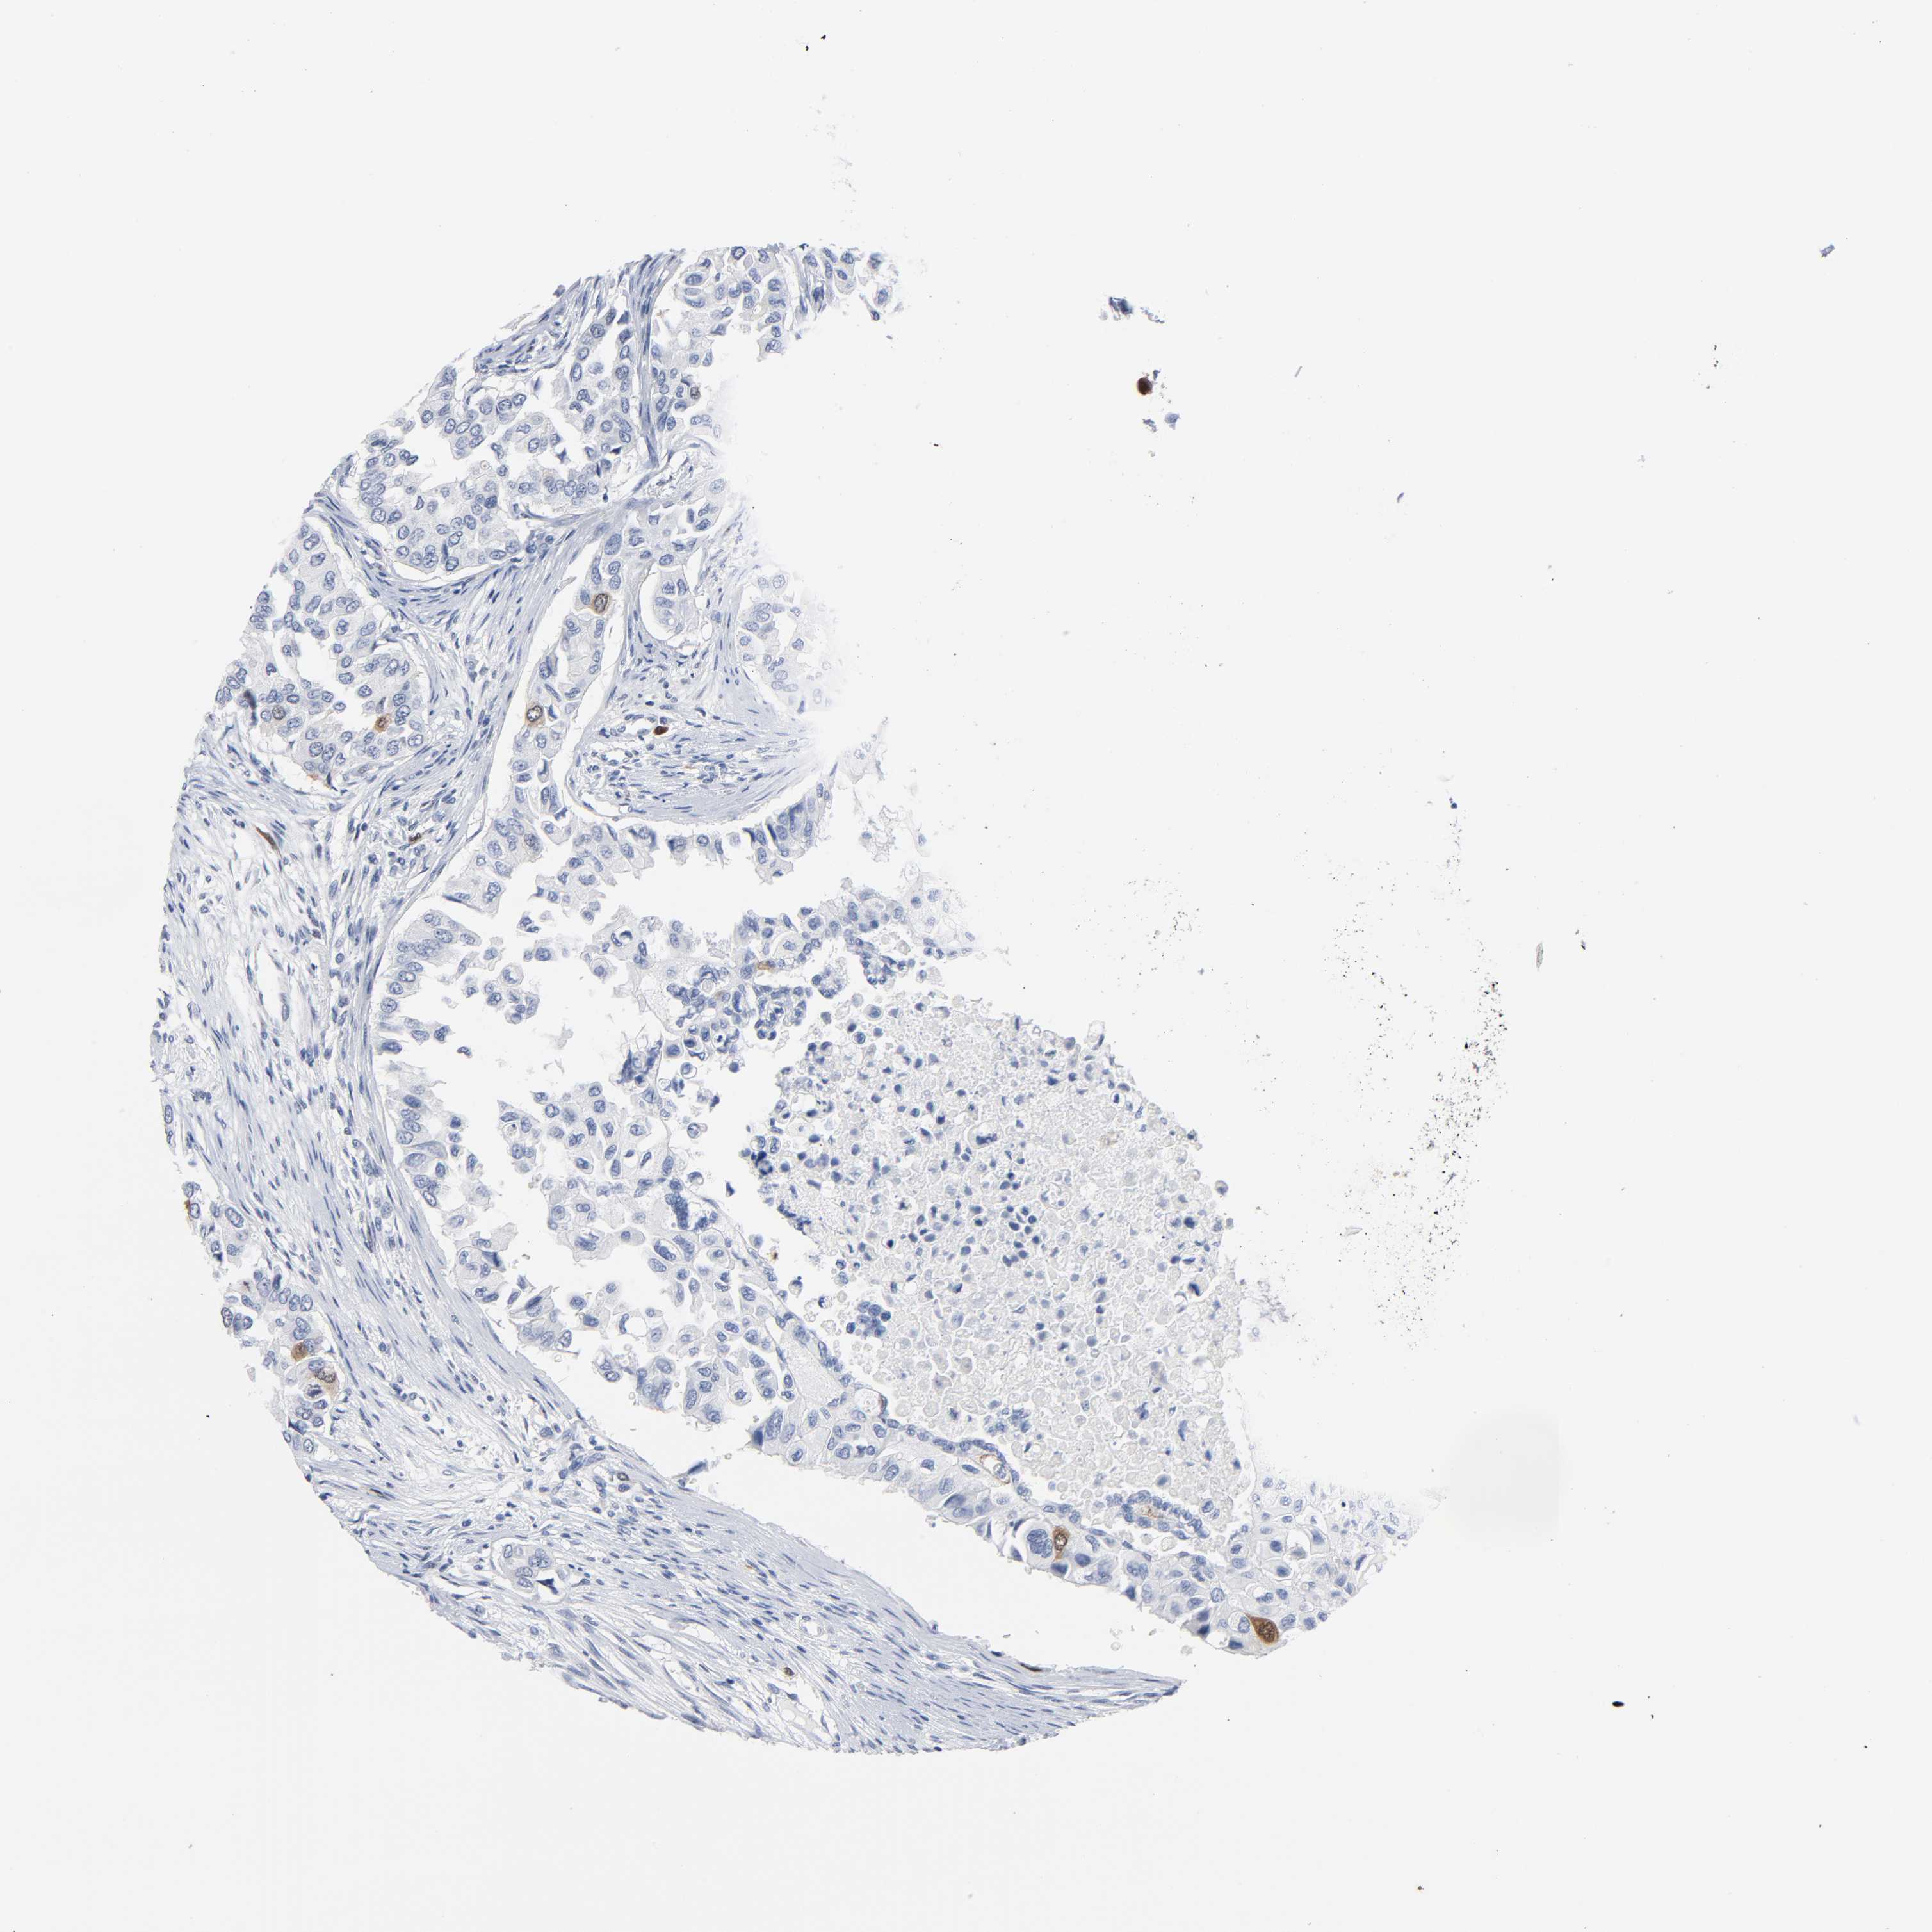

BRCA TCGA BRCA VALIDATION PROTEIN EXPRESSION

Breast cancer

Human cancer